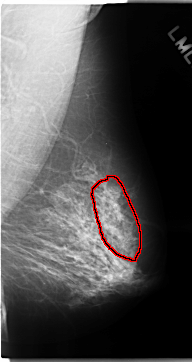

C_0133_1.RIGHT_MLO

LEFT_MLO LINES 4704 PIXELS_PER_LINE 2488 BITS_PER_PIXEL 12 RESOLUTION 50 OVERLAY

FILE: C_0133_1.LEFT_MLO.OVERLAY

TOTAL_ABNORMALITIES 1

ABNORMALITY 1

LESION_TYPE CALCIFICATION TYPE AMORPHOUS DISTRIBUTION REGIONAL

ASSESSMENT 4

SUBTLETY 3

PATHOLOGY MALIGNANT

TOTAL_OUTLINES 1

BOUNDARY